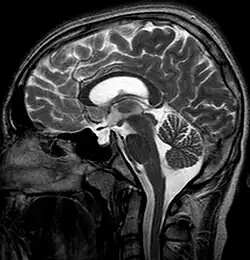

![]() Obraz MRI głowy u osoby z zespołem pustego siodła | |

Zespół pustego siodła (łac. syndroma sellae vacuae, ang. empty sella syndrome, ESS) – zespół objawów spowodowanych patologią przysadki, polegającą na przewlekłym wpuklaniu się przestrzeni podpajęczynówkowej w obręb siodła tureckiego.